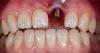

doctore Опубликовано 30 мая, 2012 Поделиться Опубликовано 30 мая, 2012 Простой и наглядный кейс.Удаление,NR Conical Connection и простая композитная коронка на простом временном циркониевом абатменте.Слайды во время и через неделю после фиксации коронки. Инаки должен быть доволен 2 Ссылка на комментарий